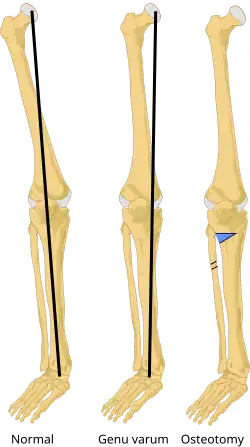

V ortopedii a traumatologii slouží k chirurgické úpravě diskrepancí kostí, např. osových, tvarových či délkových úchylek (prodlužování či zkracování), tzv. korekční osteotomie. Po osteotomii se kostní fragmety sestaví do požadovaného anatomického postavení a osteosyntézními prostředky se zajistí, např. sádrovou dlahou, zevní fixací nebo vnitřní fixací. Operační úkon lze v mnoha případech provádět miniinvazivně nebo náročněni i ve více rovinách (více řezů). Dobře indikovaná a provedená korekční osteotomie obvykle vede také ke zpomalení osteoartróz nebo k záchraně kloubů. Osteotomie je prováděna v celkové či spinální anestezii.[1][2]

Osteotomie tibie -